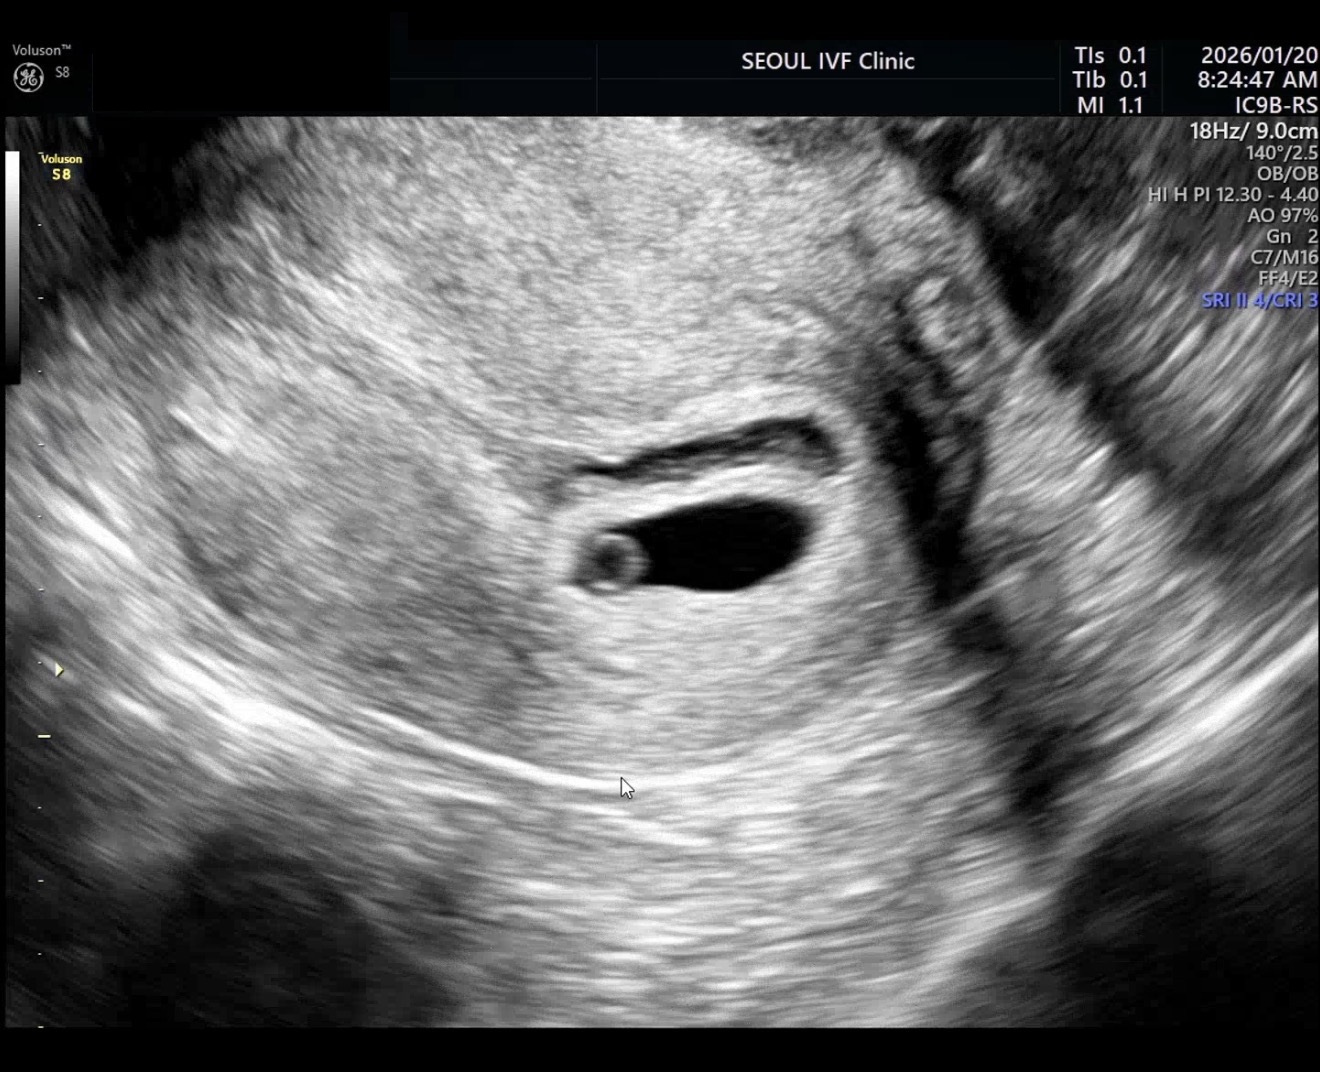

| 가슴 떨리는 임신 이야기를 공유해 주세요. | 이식 후 배아 사진을 보여주셨을 때가 가장 떨리고 뭉클한 순간이었습니다. 주사와 난자채취 등 그동안의 과정들이 한순간에 떠오르며, 그 시간이 모두 의미 있게 느껴졌습니다. |